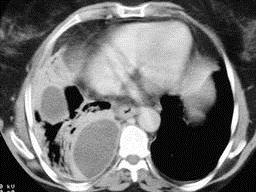

问题 男,54岁,发热、胸痛一月余,继往有酗酒史,请结合CT图像选择最可能的诊断 ( )

选项 A、肺囊虫病 B、肺癌 C、肺脓肿 D、大叶性肺炎 E、脓胸

答案 E